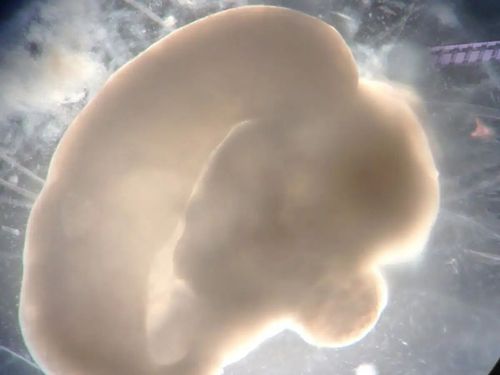

最初我使用小鼠胚胎脑细胞进行实验,将它们接种在培养皿中,任其生长。部分细胞未如预期那样紧密黏附于培养皿表面,而是脱离表面,然后相互聚集,形成了能够自组织的细胞球——外观非常近似发育早期阶段的脑组织。后来我们运用人类胚胎干细胞也成功实现了同样的培育过程。

百日类脑